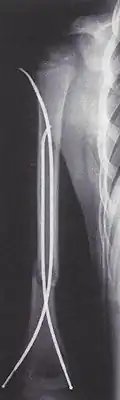

Weitere Neuerungen bei der Marknagelung waren etwa 1961 die Markraumschienung mit Bündelnagelung nach Karl H. Julius Hackethal, wodurch Übungsstabilität erzielt wurde, und der bis 1966 von H-J. Kaessmann und H. G. Weber als Modifikation des Küntscher-Nagels entwickelte Kompressionsnagel,[5] bei dem durch eine Spannvorrichtung die Knochenfragmente durch axialen Druck fixiert und somit ein Ausbohren der Markhöhle vermieden wurde.[6]